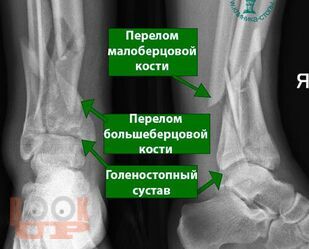

Данное учебное пособие содержит подробное описание диагностики и тактики лечения переломов дистального метаэпифиза большеберцовой кости и возможности применения внеочагового и накостного методов лечения при данных видах переломов, а также описание послеоперационного ведения больных с данной патологией, возможные осложнения и сроки реабилитации после этого вида травмы.